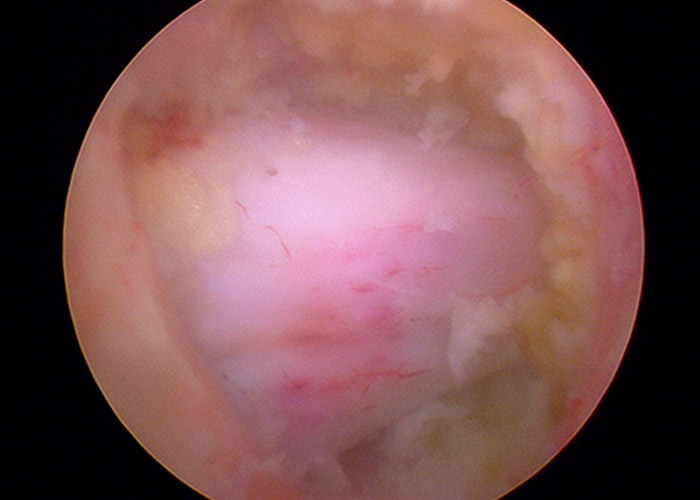

La cirugía trascurre sin incidencias y el postoperatorio trasncurrió con una mejora considerable del dolor lumbar y una sensación de liberación en las piernas.

A partir de la media hora tras la intervención, el paciente puede deambular de manera normal y sin incidencias. Se concede el alta hospitalaria a las tres horas de la cirugía..